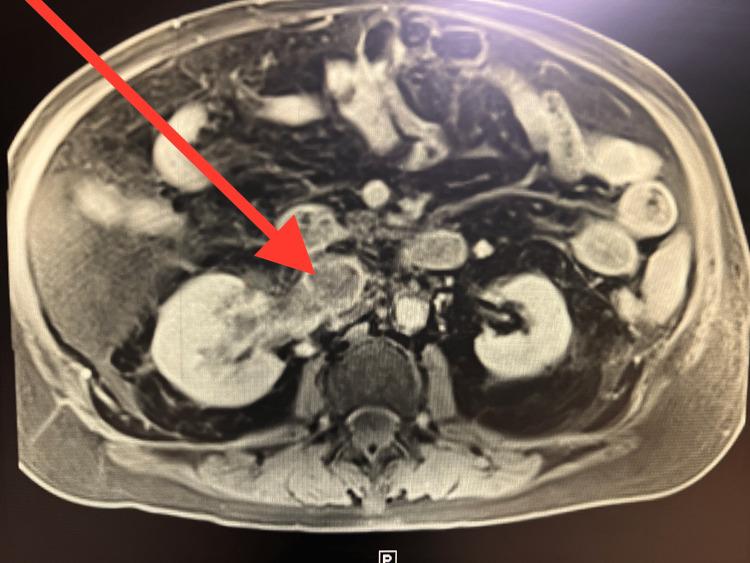

Renal cell carcinoma (RCC) is characterized by the development of kidney masses, which can lead to various long-term complications. Among the extrarenal manifestations associated with RCC, the formation of a thrombus within the inferior vena cava (IVC) is particularly prevalent due to the substantial tumor burden imposed by the kidneys. In this report, we present an exceptional case involving an 80-year-old male patient who presented with an intravascular thrombus within the inferior vena cava (IVC), which originated from RCC. The diagnosis of RCC was conclusively established through core needle biopsy and subsequent tumor marker staining. Remarkably, despite the confirmation of RCC within the IVC thrombus through biopsy and tumor marker analysis, radiological assessments failed to reveal any discernible renal cell masses within the kidneys. The patient subsequently received treatment for RCC with a combination regimen of cabozantinib and nivolumab, which resulted in a noteworthy improvement in his clinical condition. The presentation of RCC in this report is notably atypical, given that the biopsy of the thrombus yielded definitive evidence of RCC while radiological investigations did not yield any indications of renal masses or a tumor burden within the kidneys that would typically be associated with RCC.

肾细胞癌(RCC)的特征是肾脏出现肿块,这可能导致各种长期并发症。在与RCC相关的肾外表现中,由于肾脏施加的巨大肿瘤负荷,下腔静脉(IVC)内形成血栓尤为常见。在本报告中,我们介绍了一个特殊病例,一名80岁男性患者,其下腔静脉内出现血管内血栓,该血栓起源于RCC。通过芯针活检和随后的肿瘤标志物染色最终确诊为RCC。值得注意的是,尽管通过活检和肿瘤标志物分析证实IVC血栓内存在RCC,但影像学评估未能在肾脏内发现任何可辨别的肾细胞肿块。该患者随后接受了卡博替尼和纳武单抗联合方案治疗RCC,其临床状况有了显著改善。本报告中RCC的表现明显不典型,因为血栓活检产生了RCC的确切证据,而影像学检查未发现任何通常与RCC相关的肾肿块或肾脏内肿瘤负荷的迹象。